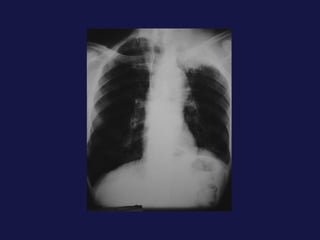

Hallazgos radiológicos. Tumor periférico. Nódulo o masa pulmonar. Bordes definidos, lobulados, irregulares, espiculados Calcificación ( focal, excéntrica ) Cavitación 1% presentan nódulos satélites. 25%  de broncoalveolares son múltiples. Adenocarcinoma y carcinoma de células alveolares.

Hallazgos radiológicos. Tumorperiférico. Nódulo o masa pulmonar. Bordes definidos, lobulados, irregulares, espiculados Calcificación ( focal, excéntrica ) Cavitación 1% presentan nódulos satélites. 25% de broncoalveolares son múltiples. Adenocarcinoma y carcinoma de células alveolares.

Adenocarcinoma ( 14-25 %). Mas frecuente en la actualidad y en aumento. 60-70 %  presentación nodular periférica  sobre todo en el lóbulo superior. No se originan en el bronquio, broncoscopia y citología de bajo rendimiento.

Adenocarcinoma ( 14-25%). Mas frecuente en la actualidad y en aumento. 60-70 % presentación nodular periférica sobre todo en el lóbulo superior. No se originan en el bronquio, broncoscopia y citología de bajo rendimiento.